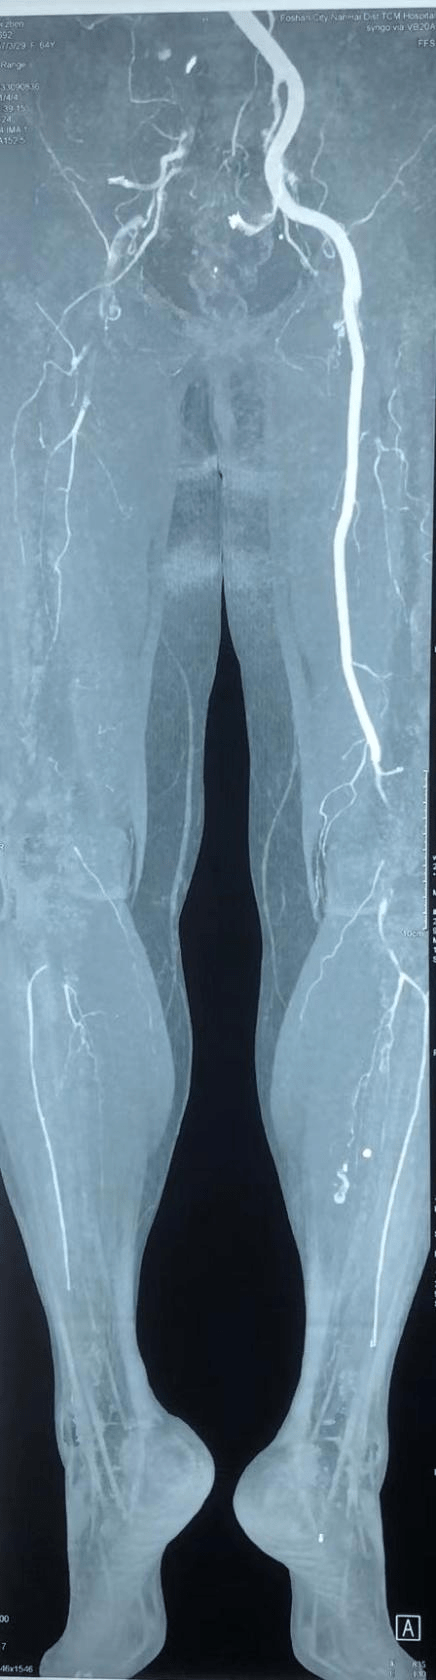

一天晚上 , 64岁的邬女士(化名)在家突发右下肢麻木 , 进而快速发展成右下肢剧烈疼痛 , 整个大腿也变得冷冰冰的 。 吓坏了的邬女士强忍疼痛来到广医二院急诊就诊 , 并由急诊收入血管外科 。 医生查体后发现整个邬女士右下肢皮温凉 , 股动脉、腘动脉、足背动脉搏动消失 。 抽血发现肌红蛋白(肌肉缺血坏死的代谢产物)已高达217.2ug/L(正常值上限61.5ug/L) 。 急诊CTA(CT血管造影)发现整个右下肢血管几乎不显影 , 右髂动脉、股动脉、腘动脉管腔充满了血栓 。

文章图片

“这么长的血栓实属罕见!”血管外科主任林少芒教授分析 , “更甚的是 , 髂动脉、股动脉是供应下肢最重要的血管 , 如果不及时进行处理 , 患者下肢难逃截肢的命运 , 性命也将危在旦夕!”

精心周全的术前准备 , 由张智辉主刀带领血管外科团队协同作战 。 专家团队经右侧腹股沟切开暴露股总动脉 , 股浅动脉和股深动脉 。 术中切开股总动脉 , 探查发现股总动脉没有血流 , 血栓充满整个管腔 。 于是在X光引导下往近端送入导丝、取栓导管至髂动脉 , 取出红色长段血栓约40cm;然后往远端送入导丝、导管至腘动脉 , 取出长段血栓约60cm 。 反复取栓直至股动脉远近端都喷血良好 , 再无血栓取出后 , 血管造影再次确认整个下肢血栓被取干净 , 且无向远端膝下和足背的动脉和对侧髂动脉脱落 。 术后查看患者右下肢皮温变暖 , 足背动脉搏动强 。